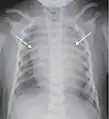

A chest radiograph showing bronchopulmonary dysplasia.